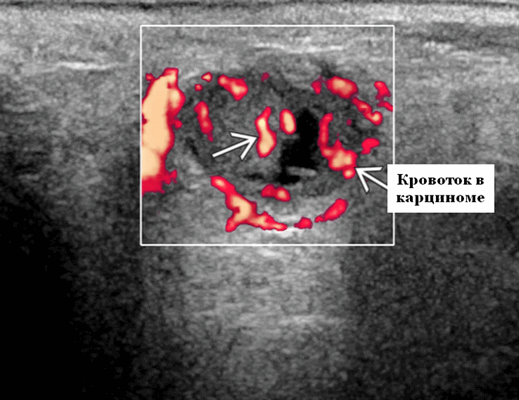

- Цветной допплер. Сигнал кровотока внутри очага поражения от умеренной до выраженной степени интенсивности

Васкуляризация злокачественных опухолей не является патогномоничным при оценке цветового допплеровского картирования или энергетического допплера, поэтому УЗИ не дает достоверную дифференциацию между доброкачественными и злокачественными опухолями слюнных желез. Однако, есть предположение, что высокая васкуляризация и значительная пиковая систолическая скорость кровотока должны вызывать подозрение на злокачественность. При обследовании пациентов в Красноярске мы пришли к выводу, что опухоли, демонстрирующие увеличение индекса сосудистого сопротивления во внутриопухолевом кровотоке, имеют повышенный риск малигнизации. Наличие метастатического осложнения, сопровождающие опухоль слюнной железы, проявляется поражением лимфатических узлов, убедительно говорит о злокачественности.